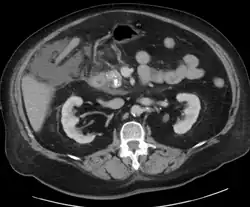

A contrast-enhanced CT scan is usually performed more than 48 hours after the onset of pain to evaluate for pancreatic necrosis and extrapancreatic fluid as well as predict the severity of the disease. CT scanning earlier can be falsely reassuring.

- Acute exudative pancreatitis on CT scan

- Calcified pancreatic duct stones with some free intra-abdominal fluid